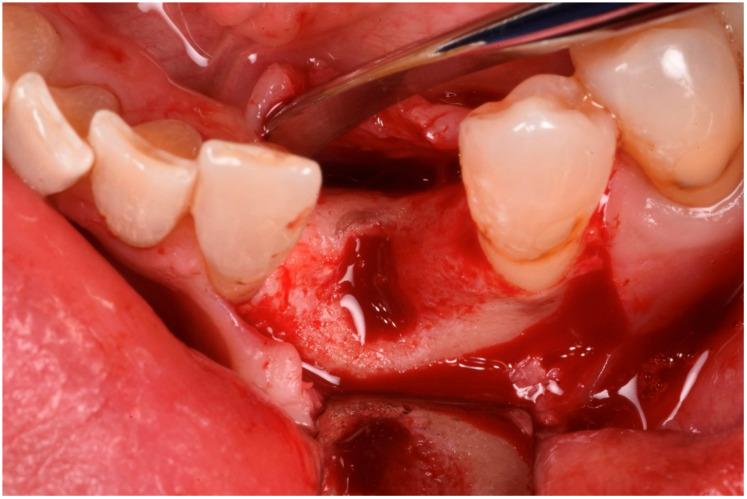

Guided bone regeneration (GBR) has represented a challenge for clinicians in the past 30 years, and the literature has well described many different surgical options such as d-PTFE membranes, titanium grids, or autogenous bone harvested from the posterior mandible. All of the previously mentioned techniques have shown a high rate of complications but, in the last decade, a new membrane made of xenogenic bone was introduced. Most of the publications regarding its application report very few and mild complications. In this article we will suggest a new application using segmented xenogenic bone sheets instead of autogenous bone to correct severe ridge deformity. : Xenogenic bone sheets have been studied extensively over the past decade and have proven effective, with a very low rate of complications when used to reconstruct bone atrophies. The technique presented in this paper aims to reduce morbidity, avoid the need for intra-oral graft harvesting, and minimize both surgical time and post-operative discomfort. : Xenogenic bone sheets of equine origin were used to reconstruct severe 3D bone defects in five patients requiring dental implants. The segmentation of the sheet allowed the operator to rebuild the missing bone walls and achieve optimal anatomy without compromise. Furthermore, using different sizes and thicknesses of the bone sheets allowed safe procedures preventing early exposure of the membranes. CBCT of the defects before and after 8 months of healing were measured with Exocad software to assess the volumetric gain. Histological analysis performed on one site showed integration of the bone lamina and live bone underneath. : In all five cases evaluated the ridge deformities were successfully corrected and all patients' implants have functioned for more than two years to date. The average horizontal bone gain in these five cases was 6.18 mm (±1.19 mm) while the vertical gain was 9.70 mm (±2.39 mm). : This new application of flex cortical sheets simplifies the surgical procedure for both operator and patient, reduces morbidity and post-operative complications, and shows promising signs for resolving complex 3D bone reconstructions.

在过去30年里,引导骨再生(GBR)一直是临床医生面临的一项挑战,文献中已经详细描述了许多不同的手术选择,如双层聚四氟乙烯(d-PTFE)膜、钛网或从下颌后部获取的自体骨。上述所有技术都显示出较高的并发症发生率,但在过去十年中,一种由异种骨制成的新型膜被引入。关于其应用的大多数出版物报告的并发症很少且很轻微。在本文中,我们将提出一种使用分段异种骨片代替自体骨来矫正严重牙槽嵴畸形的新应用。:在过去十年中,异种骨片已被广泛研究,并已被证明是有效的,用于重建骨萎缩时并发症发生率非常低。本文介绍的技术旨在降低发病率,避免口内取骨的需要,并将手术时间和术后不适降至最低。:使用马源异种骨片为五名需要种植牙的患者重建严重的三维骨缺损。骨片的分段使手术者能够重建缺失的骨壁并实现最佳解剖结构而不受影响。此外,使用不同尺寸和厚度的骨片可进行安全操作,防止膜过早暴露。使用Exocad软件测量愈合8个月前后缺损的锥形束计算机断层扫描(CBCT),以评估体积增加情况。对一个部位进行的组织学分析显示骨板与下方活骨的整合。:在评估的所有五例病例中,牙槽嵴畸形均得到成功矫正,所有患者的种植体至今已正常使用两年多。这五例病例的平均水平骨增量为6.18毫米(±1.19毫米),而垂直增量为9.70毫米(±2.39毫米)。:这种柔性皮质骨片的新应用简化了手术者和患者的手术过程,降低了发病率和术后并发症,并显示出解决复杂三维骨重建问题的良好前景。